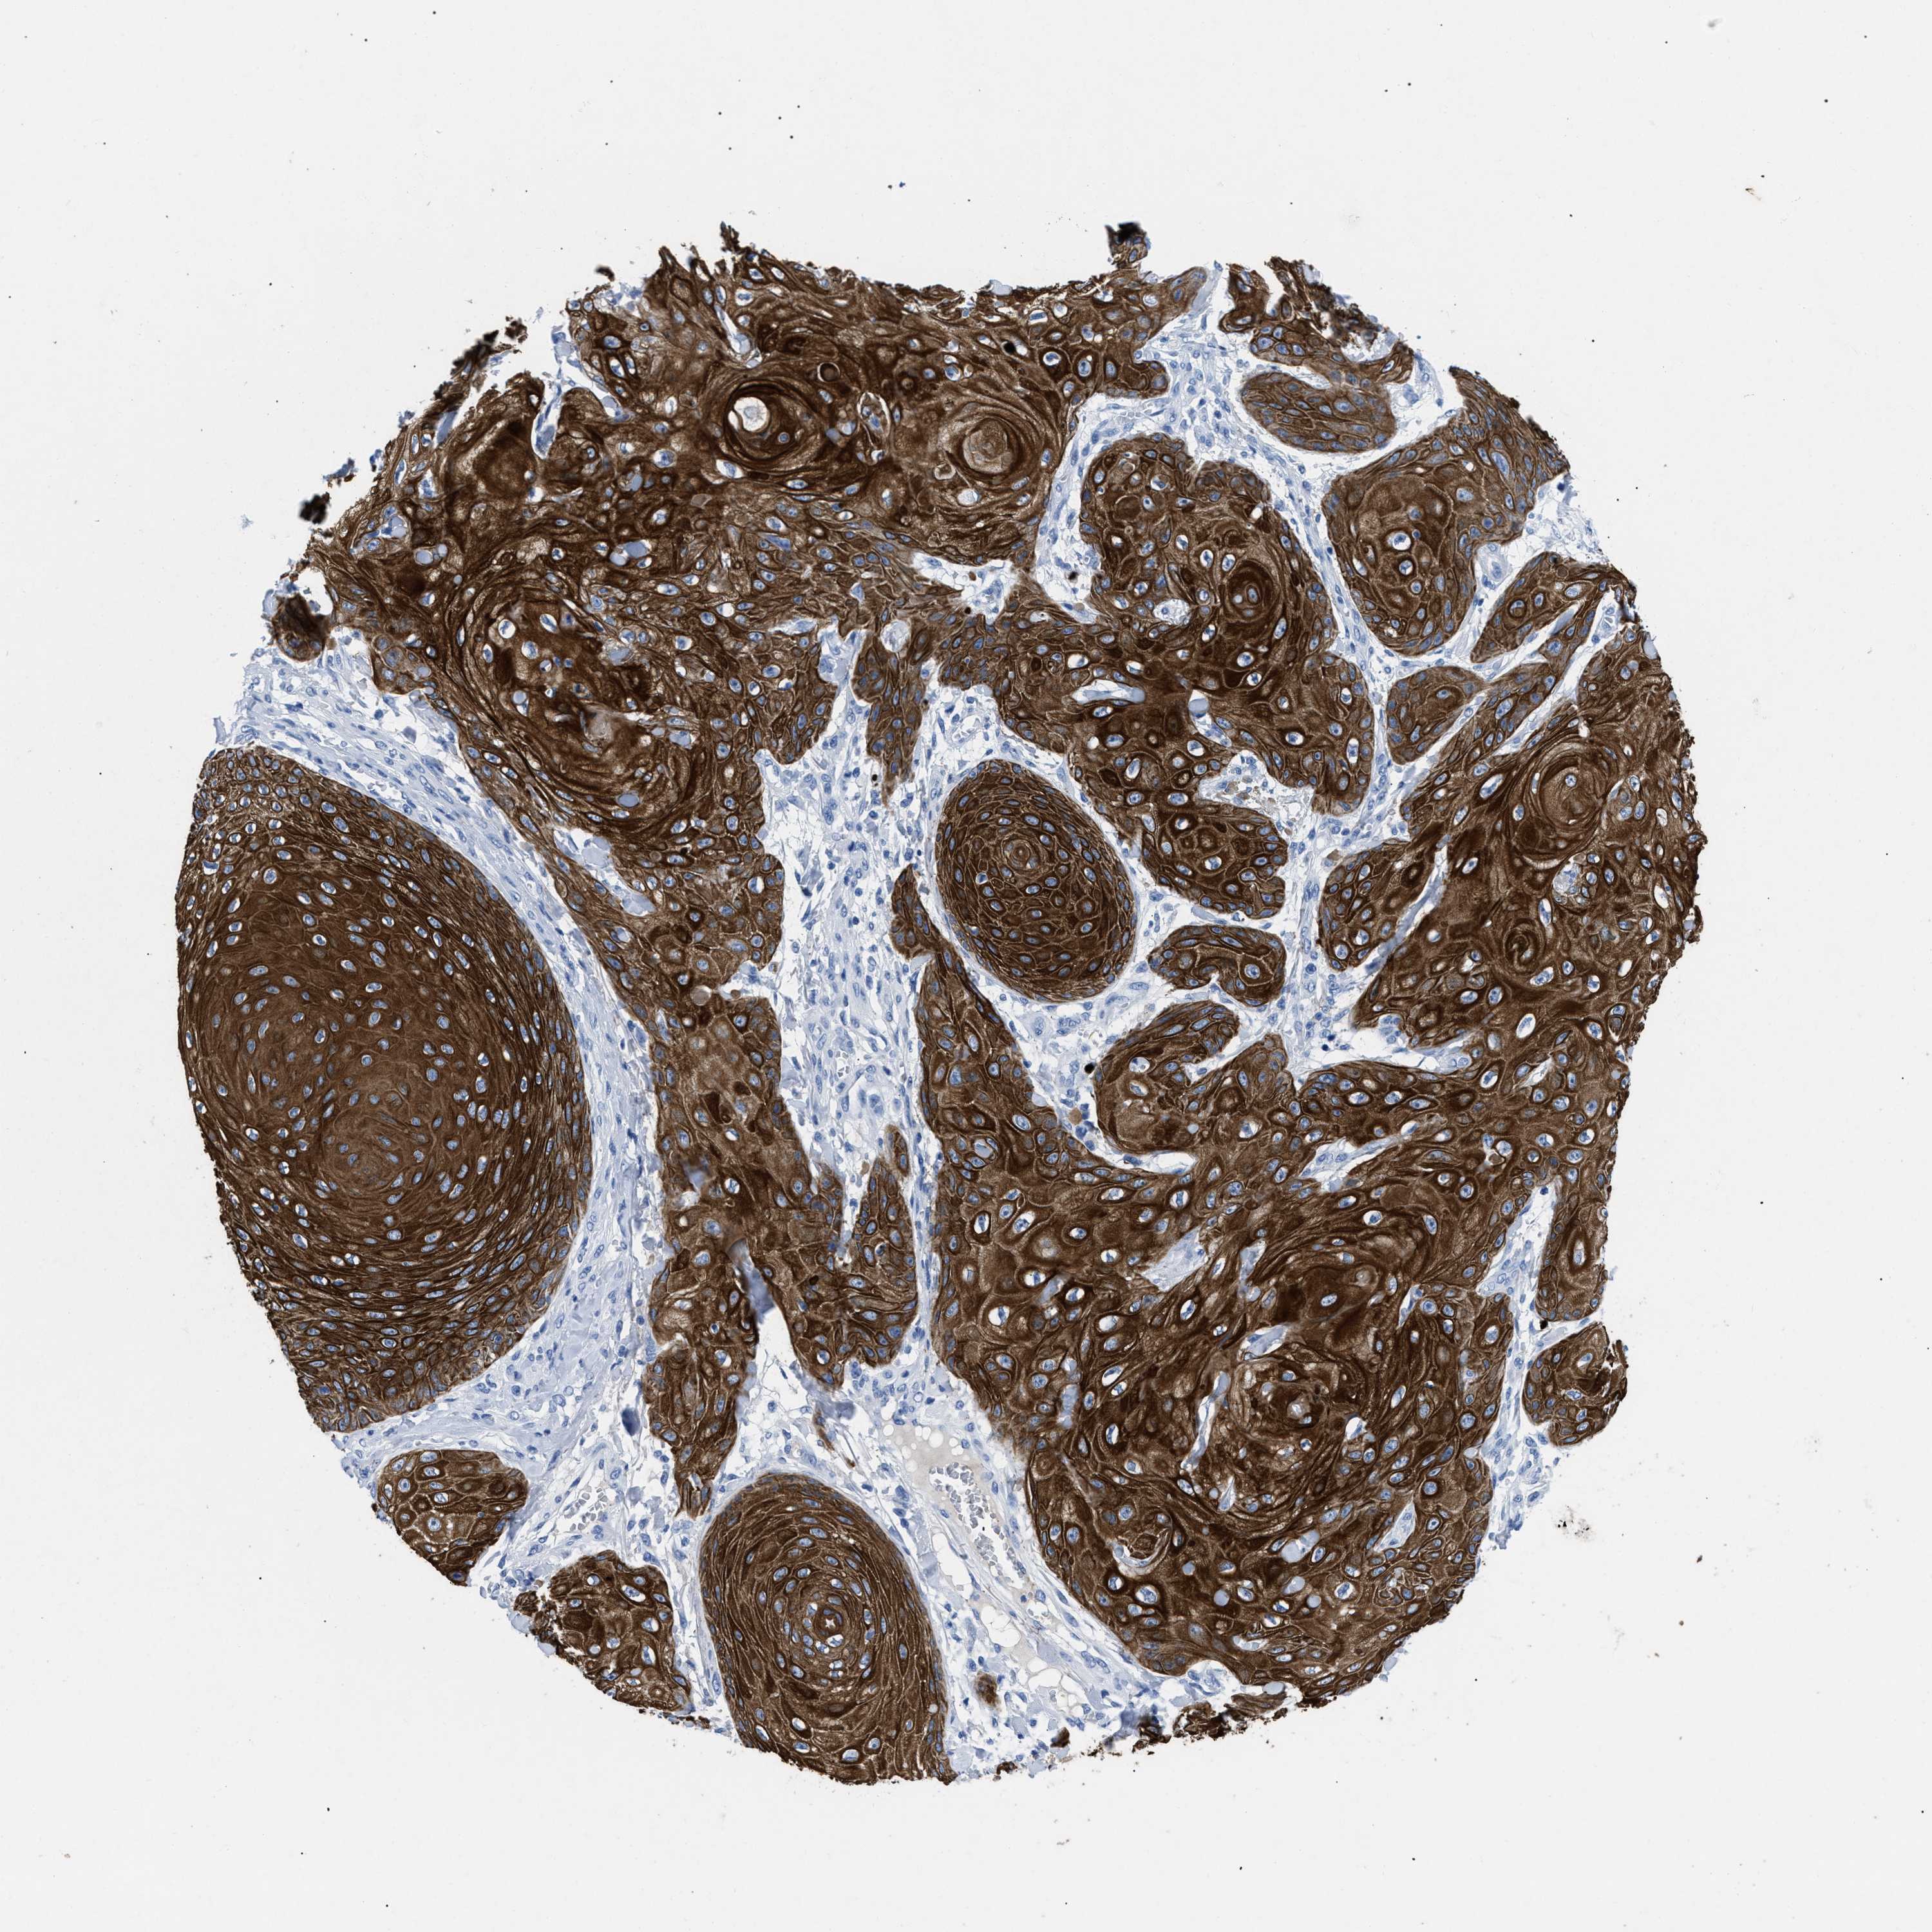

SKIN CANCER - Protein expressioni

A mouse-over function shows sample information and annotation data. Click on an image to view it in a full screen mode. Samples can be filtered based on level of antibody staining by selecting one or several of the following categories: high, medium, low and not detected. The assay and annotation is described here.

Antibody stainingi

Antibody staining in the annotated cell types in the current human tissue is reported as not detected, low, medium, or high, based on conventional immunohistochemistry profiling in selected tissues. This score is based on the combination of the staining intensity and fraction of stained cells.

Each image is clickable and will lead to virtual microscopy that enables deeper exploration of all samples and also displays staining intensity scores, fraction scores and subcellular localization as well as patient and tissue information for each sample.

Antibody HPA018216

Antibody HPA019173

Staining

High

Medium

Low

Not detected

Intensity

Strong

Moderate

Weak

Negative

Quantity

>75%

75%-25%

<25%

None

Location

Nuclear

Cytoplasmic/membranous

Cytoplasmic/membranous,nuclear

Squamous cell carcinoma in situ, NOS

Squamous cell carcinoma, NOS

Squamous cell carcinoma, metastatic, NOS

Basal cell carcinoma